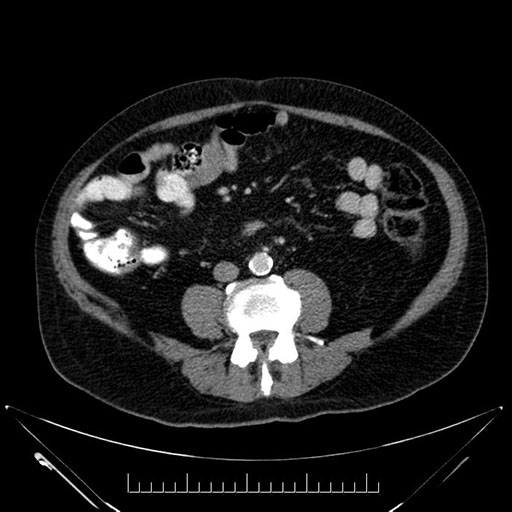

Whipple (pancreaticoduodenectomy) [case 7]

Imaging Analysis

Look through the patient's CT scan to identify any areas of concern for the necessary procedure.

Based on your CT findings, which issue(s) would give reason for "planned slowing down moment(s)" in this case?

Considering a standard Whipple procedure, what step(s) of the operation would you do differently in this case?